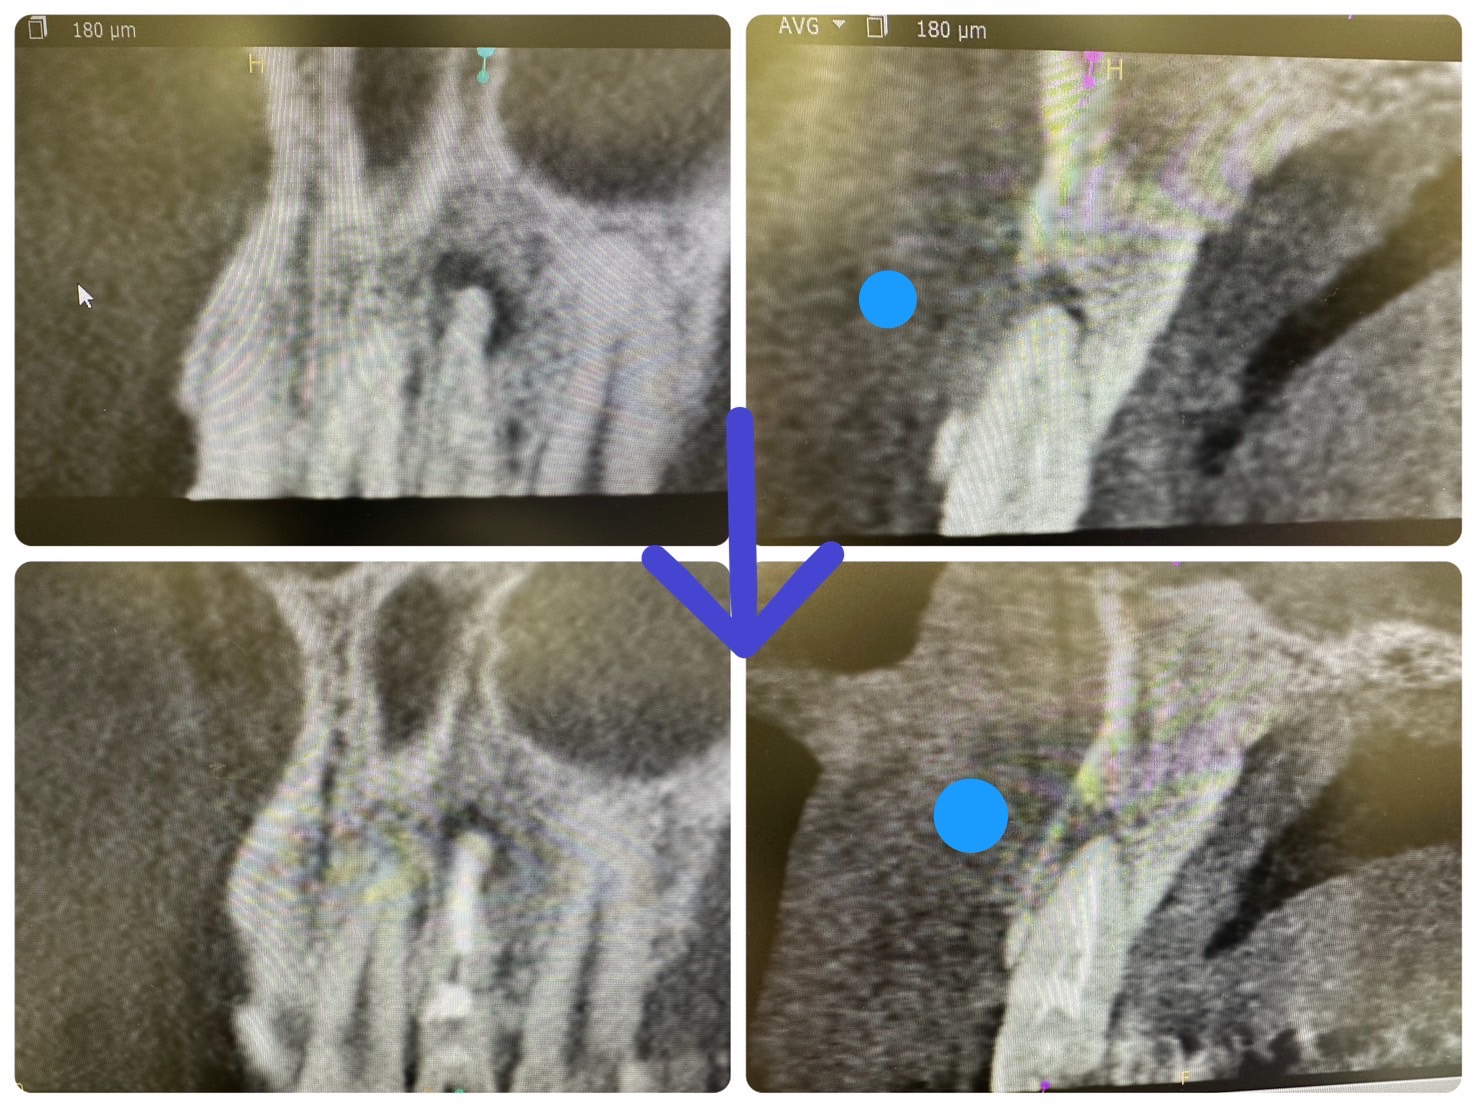

本日の細やかな収穫、根管治療単根

4ヶ月経過、50代、MTA根充

ここまで縮小すれば、あとは自然治癒力で治る!

長さ計測、殺菌の繰り返し、その前に咬合調整が重要ストレート根だから簡単

頬側骨板、バルコニーの再生!